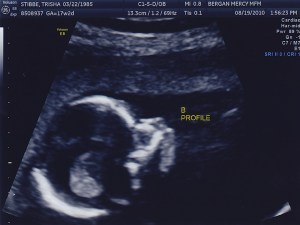

Today was the BIG appointment!!! They were able to confirm that the babies are identical. Yay!